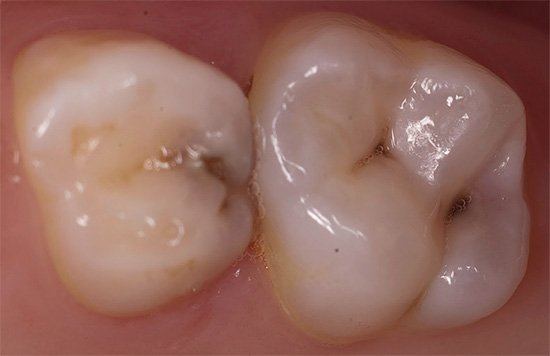

Opzioni di sviluppo della pulite per diversi gruppi di denti

La pulite può svilupparsi su qualsiasi dente, ma ci sono alcuni gruppi di denti che sono spesso inclini a tale lesione. Il primo posto nella frequenza dell'occorrenza è occupato dai primi molari o, altrimenti, dal sesto dente, che appaiono tra i primi (a 6 anni) e si trovano nella zona più non protetta, spesso con fessure profonde e chiuse (fossa). Quando compaiono delle macchie in queste aree del bambino, i genitori non capiscono immediatamente di cosa si tratta, ma con l'approfondimento del processo ogni giorno si avvicina al momento in cui il bambino inizia a lamentarsi di un forte dolore spontaneo nel dente - questa è già pulpite.

Tuttavia, non bisogna dimenticare che, nonostante tale "fortuna" dei denti anteriori inferiori per quanto riguarda i rischi di sviluppare complicanze della carie (pulpite e parodontite), i denti inferiori sono più inclini a depositare tartaro su di loro proprio a causa della stessa saliva altamente salina ( vedi l'esempio nella foto).